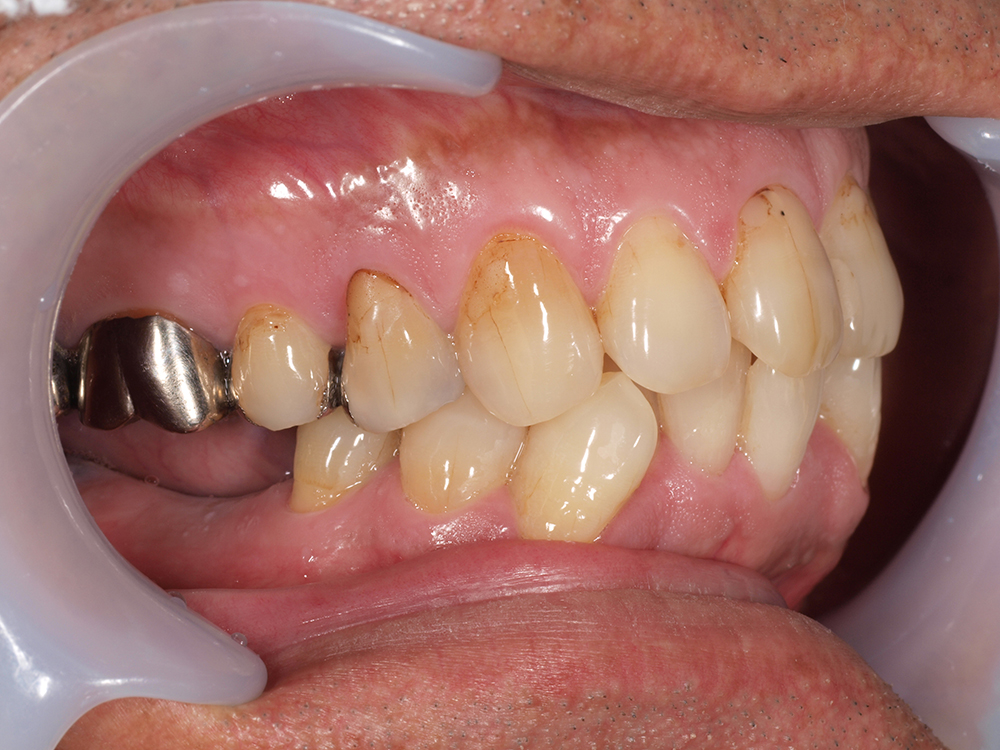

58歳 男性 歯科医療関係者紹介

- 主訴

- 右下を抜歯して噛めない

- 処置内容

- インプラント2本埋入

- 治療費用

- 約80万円(税込)

- 治療期間

-

8か月

仮歯完成まで5か月(この時点で噛めます)、+3か月で最終素材へ

- リスク

- 上部構造物、仮歯の破折、術後の腫れ(3日)、人工歯根脱落リスクがあります